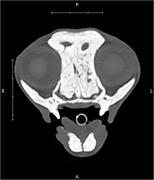

Case summary: A 5-year-old neutered male domestic medium-hair cat was referred to the internal medicine department with upper respiratory signs and limb pain. Computed tomography (CT) revealed diffuse osteosclerosis, showing severe osseous thickening of the nasal turbinates and near-occlusion of the nasal passages. No new or healed fractures were observed. Additional diagnostic tests revealed no infectious or neoplastic causes. The cat was treated supportively for pain and nasal inflammation. One year after the diagnosis, the cat was described as having an acceptable quality of life at home, despite ongoing clinical signs of nasal congestion.

Relevance and novel information: Chronic upper airway congestion is a common presenting complaint in feline patients. This report describes the imaging findings in a cat in which upper airway signs were due in part to systemic bone pathology. Previous reports suggest that the most common causes of chronic nasal congestion are acquired conditions with poor prognosis, such as lymphoplasmacytic rhinitis, neoplasia, or fungal infection. Diseases that cause diffuse osteosclerosis in cats are poorly understood. This report describes a case of diffuse osteosclerosis in a young cat with no other known comorbidities. The clinical picture is similar to descriptions of an osteosclerotic bone disorder in humans commonly referred to as autosomal dominant osteopetrosis type 1. Since no targeted treatments are available to reverse the osseous changes, the patient was treated supportively with pain management and corticosteroids. Recent developments in our understanding and treatment of similar human diseases may guide future advances in veterinary medicine.